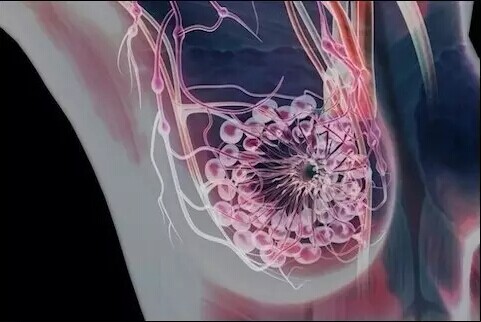

女性乳房、乳腺